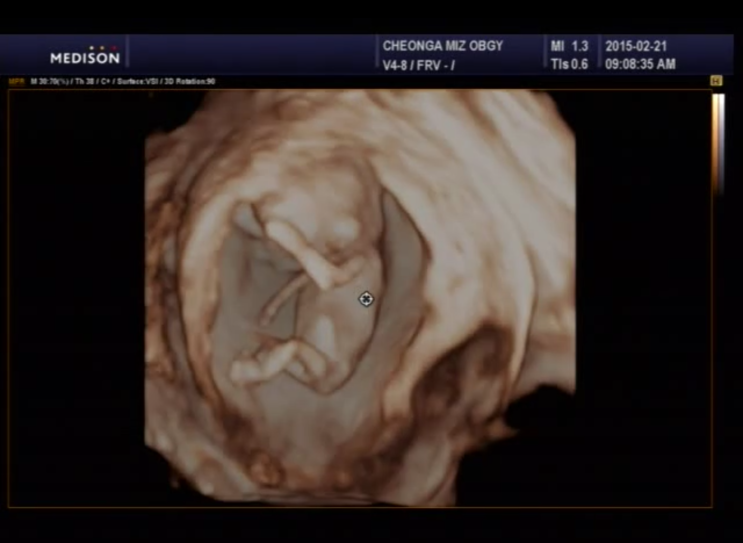

12주기적 - 1차기형검사 정상

울리언이가 너무보고싶어서 본래는 오늘 병원가는날인데 토요일날 갓다왓어요 ㅋㅋㅋ 갓다오길...